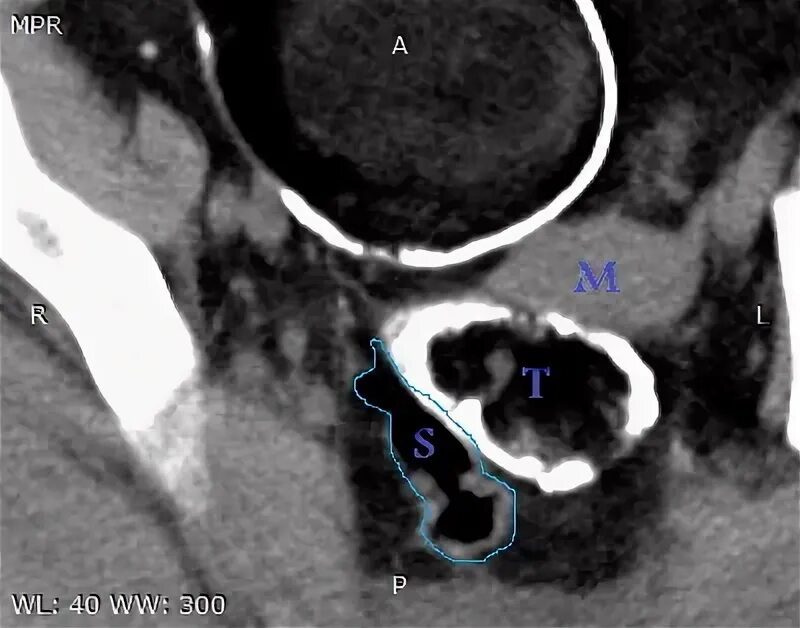

Киста уменьшается в размере